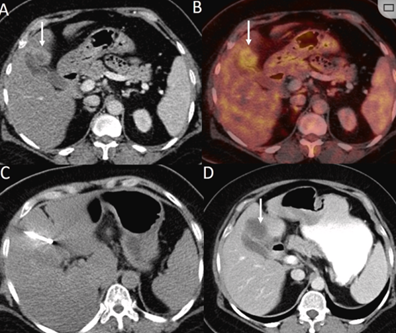

79 歲男性,肝轉移(結直腸癌)腫瘤的完全消融病例

( a ) 軸向 MRI 和 ( b ) 軸向 CT 顯示肝S8段有一個16mm的病灶,鄰近肝緣。( c )冷凍消融期間CT顯示放置了2個冷凍探針,低密度冰球包圍病灶。(d)術后1個月隨訪 CT顯示冰球對應的壞死區域,未見復發。(f)與基線影像(g)相比,12個月后的FDG-PET/CT顯示未見FDG攝取。

(a)軸向CT顯示病變位置毗鄰心臟和上腔靜脈(黑色箭頭)。1個月后的軸向(e)和冠狀位(f)增強CT掃描顯示低密度區域,由于肉芽組織反應引起的邊緣增強。

技術成功100%,92% 的病灶中觀察到腫瘤完全消融。16 名患者 (33%) 出現局部復發。10 名患者 (20%) 因局部復發或腫瘤消融不完全而接受二次冷凍消融術。